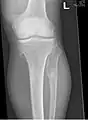

multiple osteochondromas around the knee

It is characterized by the growth of cartilage-capped benign bone tumours around areas of active bone growth, particularly the metaphysis of the long bones. Typically five or six exostoses are found in upper and lower limbs. Image depicts adult regrowth after knee replacement.

The diagnosis of HMO is based upon establishing an accurate correlation between the above-mentioned clinical features and the characteristic radiographic features. Family history can provide an important clue to the diagnosis. This is supplemented by testing for the two genes in which pathogenic variants are known to cause HMO namely EXT1 and EXT2. A combination of sequence analysis and deletion analysis of the entire coding regions of both EXT1 and EXT2 detects pathogenic variants in 70–95% of affected individuals.[3][4] The hallmark of radiographic diagnosis is the presence of osteochondromas at the metaphyseal ends of long bones in which the cortex and medulla of the osteochondroma represent a continuous extension of the host bone. This is readily demonstrable in radiographs of the knees.[3][1]